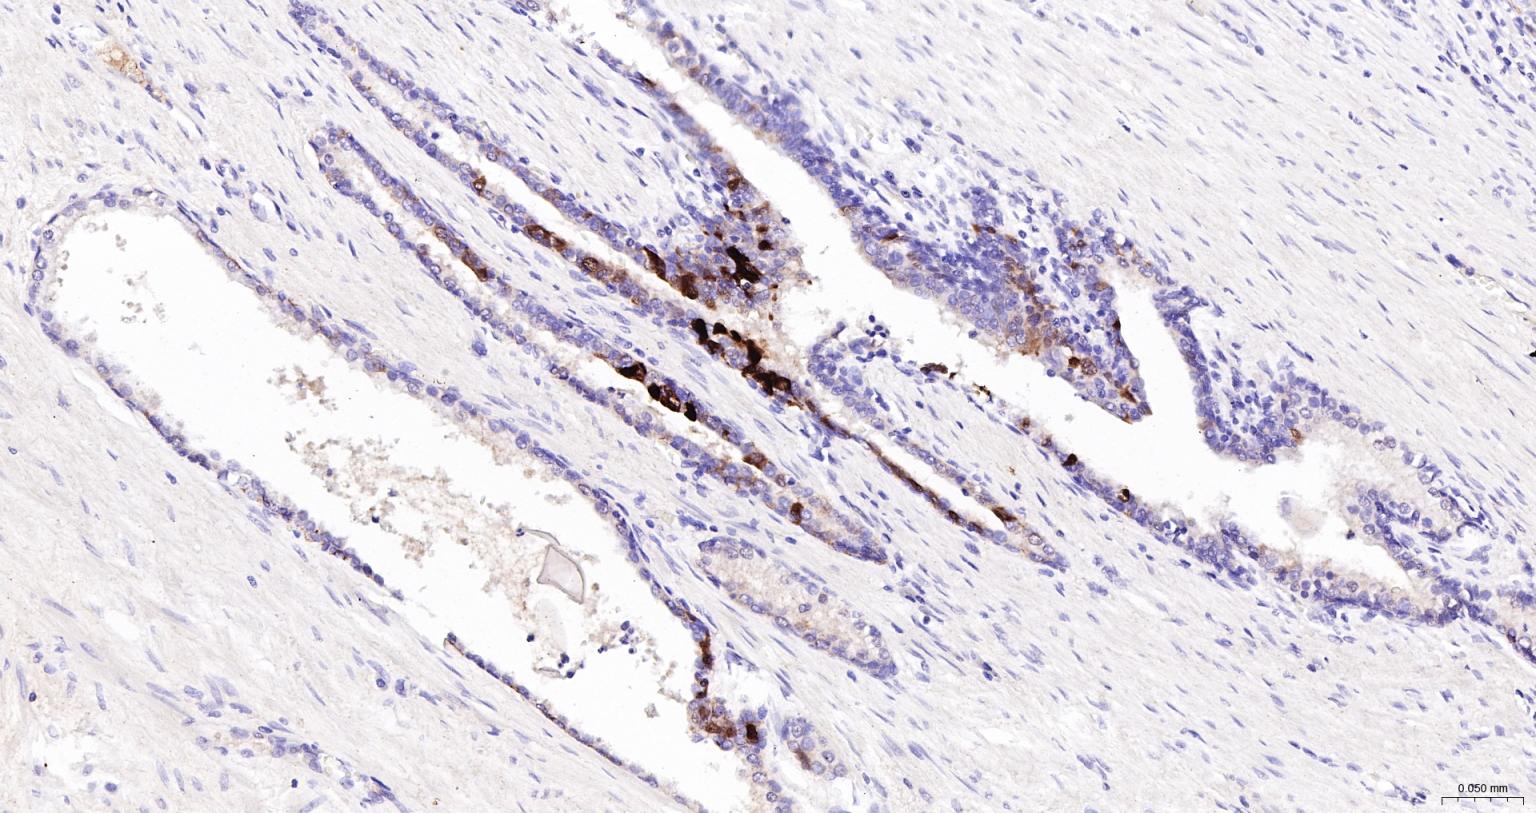

Paraformaldehyde-fixed, paraffin embedded Human Prostate; Antigen retrieval by boiling in sodium citrate buffer (pH6.0) for 15 min; The section was incubated with SERPINB3 Monoclonal Antibody, Unconjugated (bsm-43190R) at 1:200 overnight at 4°C, followed by conjugation to the bs-0295G-HRP and DAB (C-0010) staining.

Paraformaldehyde-fixed, paraffin embedded Human Tonsil; Antigen retrieval by boiling in sodium citrate buffer (pH6.0) for 15 min; The section was incubated with SERPINB3 Monoclonal Antibody, Unconjugated (bsm-43190R) at 1:200 overnight at 4°C, followed by conjugation to the bs-0295G-HRP and DAB (C-0010) staining.

Paraformaldehyde-fixed, paraffin embedded Human Cervical Cancer; Antigen retrieval by boiling in sodium citrate buffer (pH6.0) for 15 min; The section was incubated with SERPINB3 Monoclonal Antibody, Unconjugated (bsm-43190R) at 1:200 overnight at 4°C, followed by conjugation to the bs-0295G-HRP and DAB (C-0010) staining.